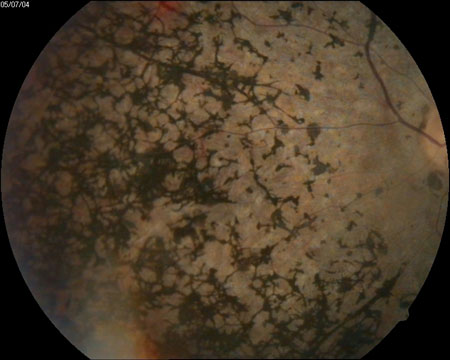

Afecta inicialmente a la visión nocturna ocasionando una lenta o deficiente adaptación a la oscuridad, existiendo dificultad para ver en lugares con poca iluminación. Es lo que se conoce como ceguera nocturna o hemeralopia. Comienza entonces el depósito de pigmento en la retina periférica (Figura 1), pero la persona afectada puede no ser consciente de estos cambios que reducen su campo visual.

Figura 1